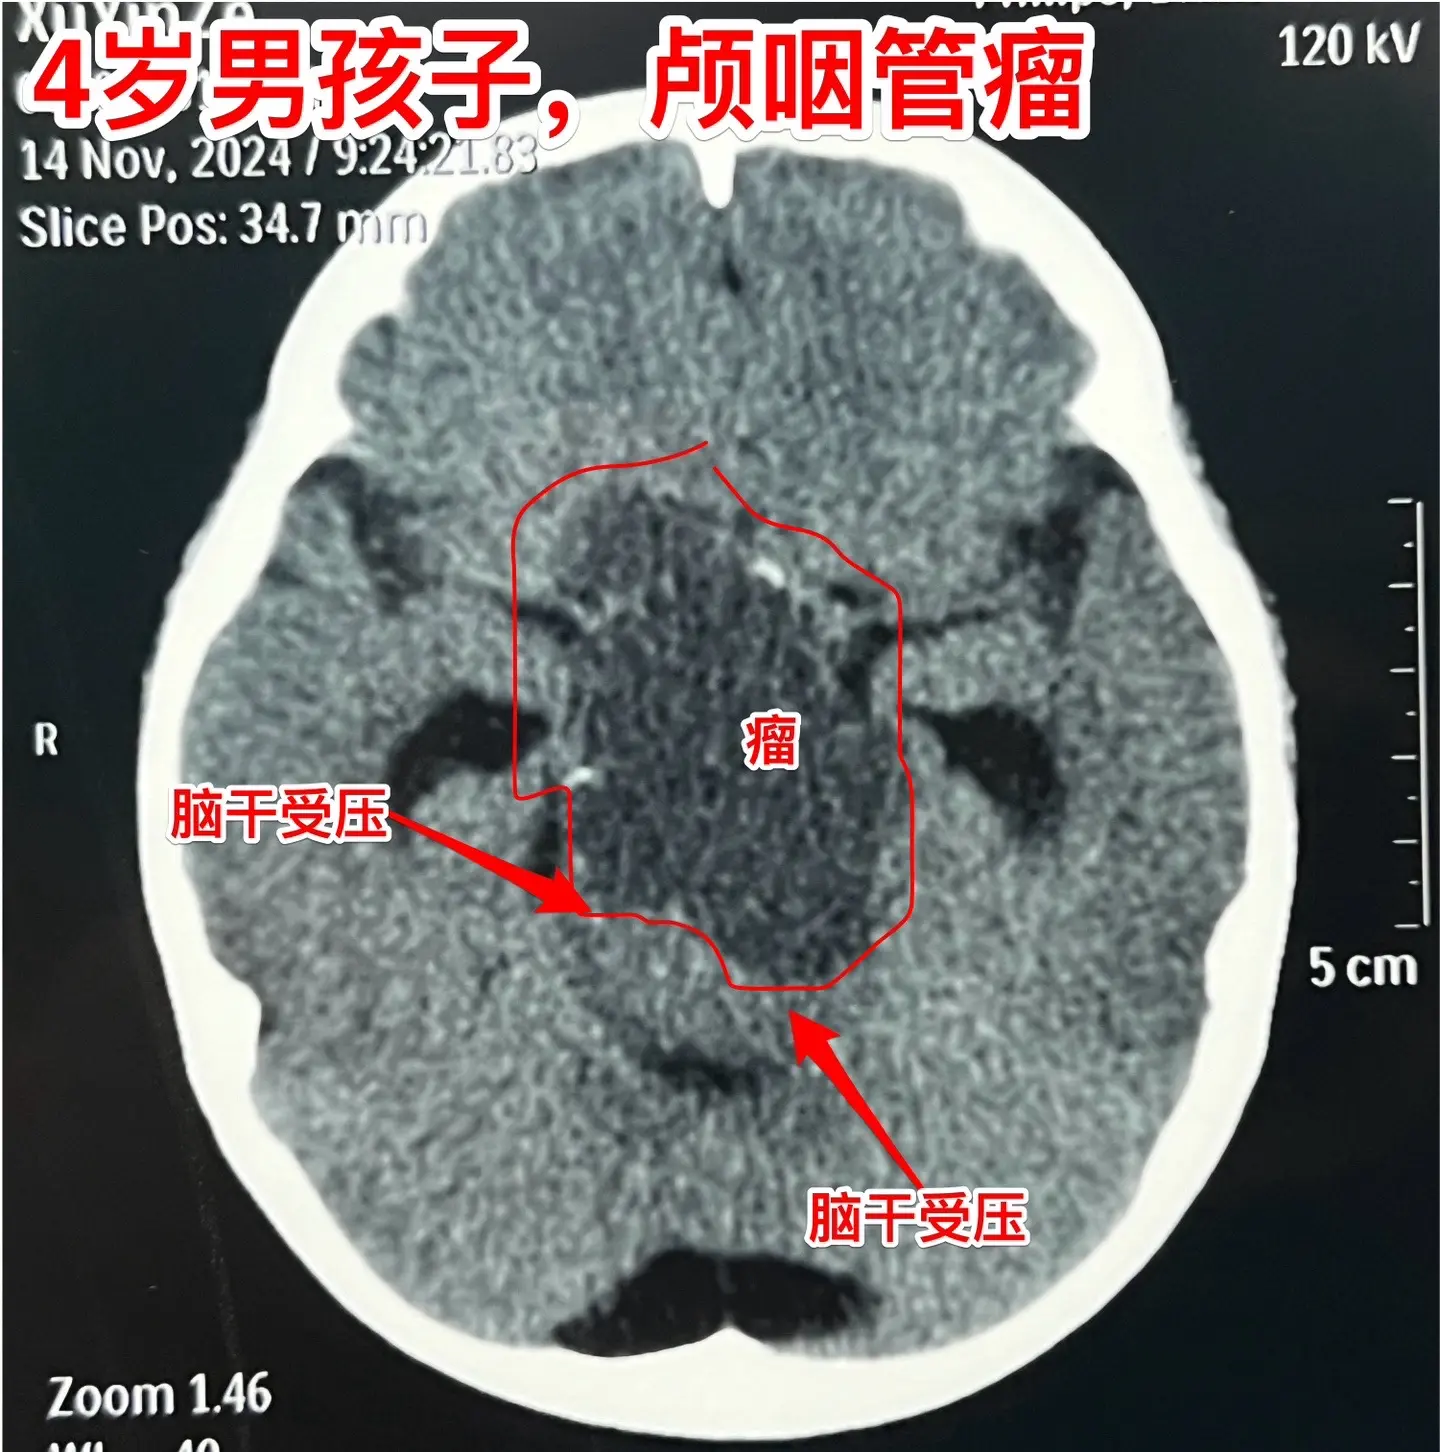

四岁男孩子右侧上下肢有点偏瘫症状!四岁苏州市男孩子出现视力下降、左侧眼...